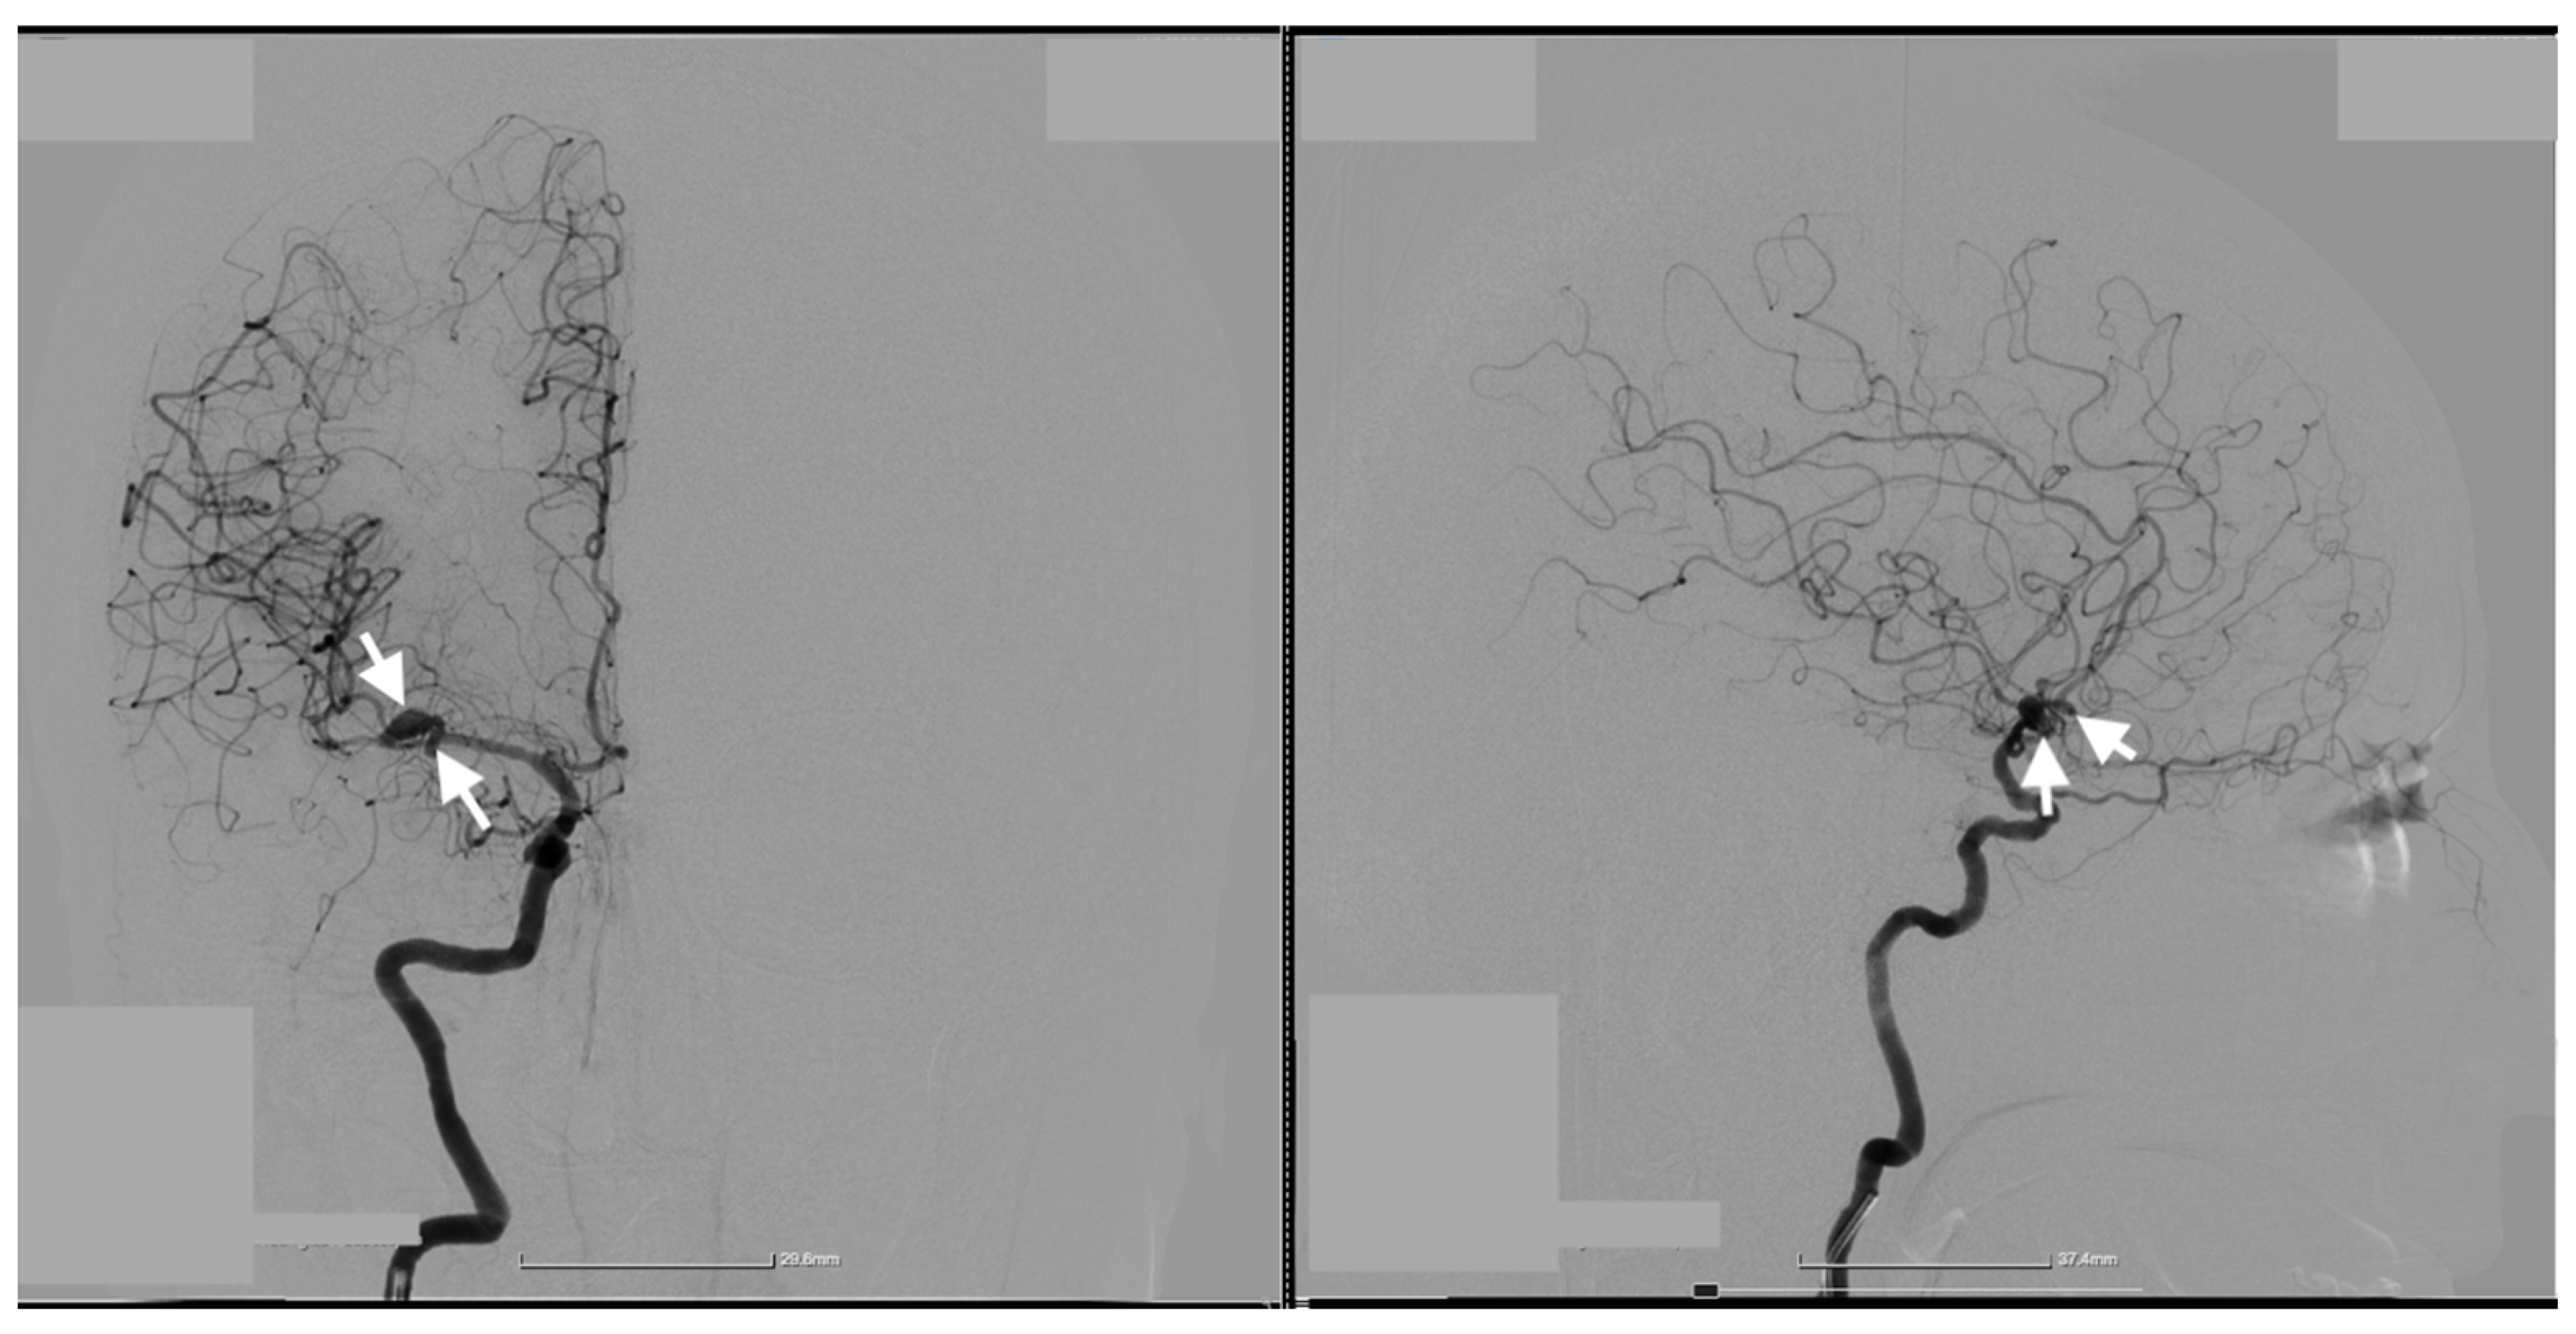

Cerebral angiography confirmed the presence of 2 ruptured saccular aneurysms at the bifurcation of the M1 segment of the right MCA (Figure 1, Figure 2 and Figure 3).

Figure 1. Preoperative two-dimensional (2D) digital subtraction angiography. Frontal (left image) and Profile (right image) 2D DSA shows the two kissing aneurysms located at the bifurcation of the M1 segment of the right MCA. The white arrows indicate the precise location of the aneurysms, highlighting their proximity and shared arterial walls.